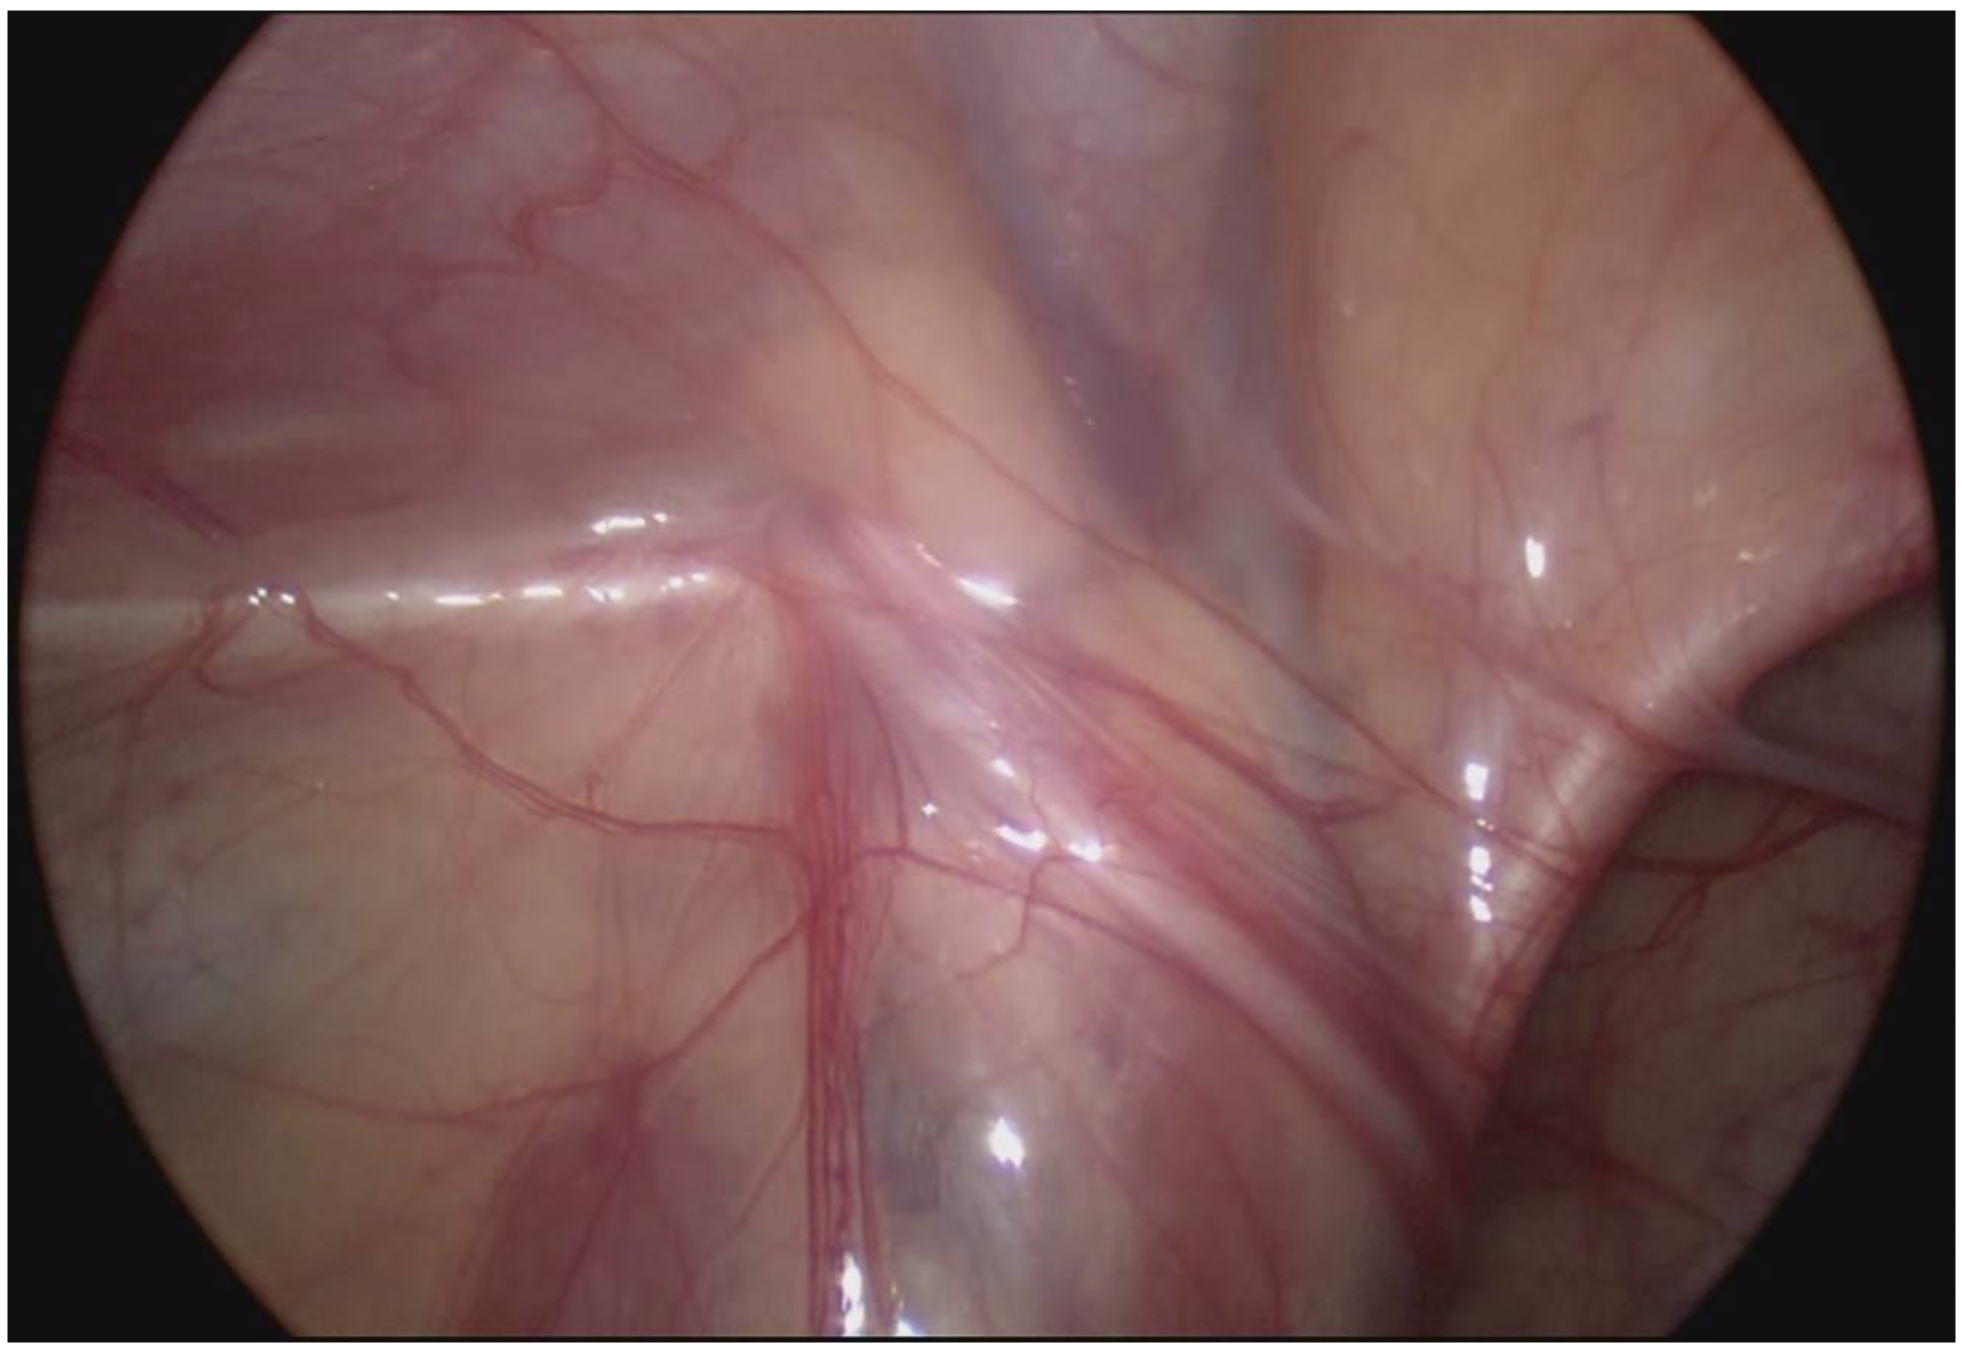

2. Case Description